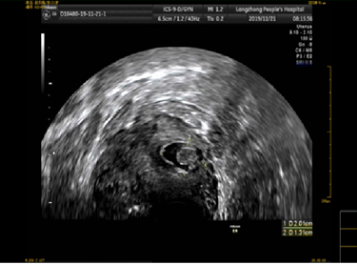

病例回顾:患者赵女士,31岁,有再生育要求。因“停经41天,阴道少量流血12天” 于2019年11月21日08时59分入院。患者既往有院外剖宫产手术史。入院前阴道超声提示:宫前壁切口处肌壁内查见一大小约2.0*32.5px的孕囊样回声,内未见卵黄囊及胚芽,CDFI显示周边可见较丰富血流信号,该处肌层菲薄,厚约3.75px。遂收住住院治疗。入院诊断:剖宫产术后子宫瘢痕妊娠(3型)。

该患者孕囊位于子宫切口处肌壁内,且该处肌层菲薄,厚约3.75px(如图1,2,3)。出血风险及子宫穿孔风险极大。为了保留生育功能,确保患者生命安全,我院妇科积极发起多学科联合诊疗(MDT)会议,特邀请放射科、麻醉科、超声科等相关科室开展讨论,一致决定先由放射科行子宫动脉栓塞术并灌注甲氨蝶呤杀胚治疗(微创介入),72小时之内再行清宫术。最终,该患者在放射科顺利完成甲氨蝶呤灌注和双侧子宫动脉栓塞(如图4-5)的情况下,第二天由妇科在超声科床旁监护下成功完成清宫术(如图6),宫腔镜检查宫腔及切口处无异常。术中出血仅有5ml(出血量较常规清宫术明显减少),并于术后第三天康复出院。

图2:切口妊娠-孕囊大小